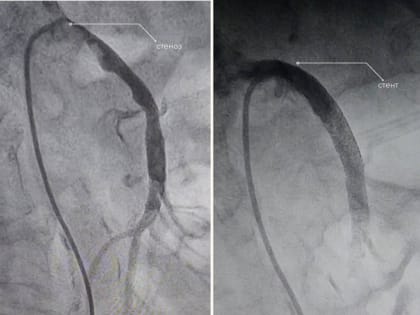

В Нижневартовске спасли женщину с редким заболеванием

Врачи окружной Нижневартовской больницы успешно провели операцию у женщины с заболеванием, которое встречается у 2-4% пациентов.